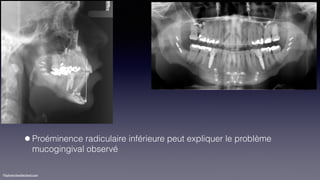

•Restauration implantoportée 36 et 46

•Recommandation d’une greffe gingivale au buccal

de 31, 41

KeBiDu181214

•Proéminence radiculaire inférieure peut expliquer le problème

mucogingival observé

©sylvainchamberland.com